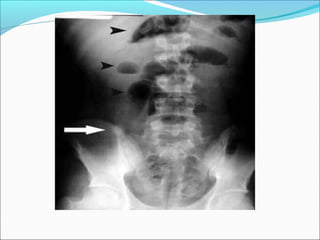

Diagnóstico por imagem

Radiografia

Fecalito

Massas inflamatórias

Distensão/alargamento vísceras

Calcificações

Iléo paralítico